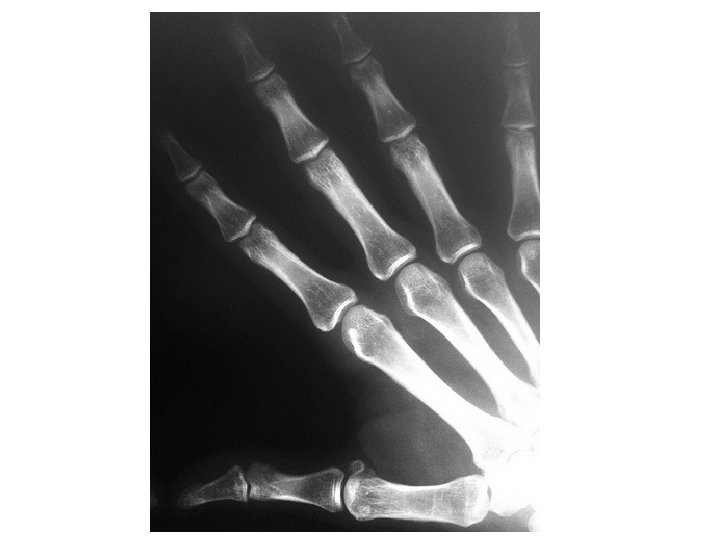

Radiological terminology -1 • Imaging techniques: – X-ray – computed axial tomography (CAT) CT scan – Ultrasound scans (Sonography) – Magnetic Resonance Imaging (MRI)

Radiological terminology - 2 • X-rays depend on the difference in absorption of xrays by various tissues. – Radiopaque means a lot of x-ray energy is absorbed (causing the fils to be WHITE) Like: bone, teeth, metal implants – Radiolucent means little energy is absorbed (causing the film to be BLACK) Like: air, fat

Radiological terminology - 3 • Plain film – X-ray without the use of artificial contrast. • Contrast film – X-ray where radiopaque contrast has been introduced into a cavity, space or vessel. • Examples: – – Angiogram (x-ray of arteries, e. g. of the heart) Venogram (x-ray of veins, e. g. of the legs) Barium meal (x-ray of the upper digestive tract) Myelogram (x-ray of the spinal cord and spinal nerves)